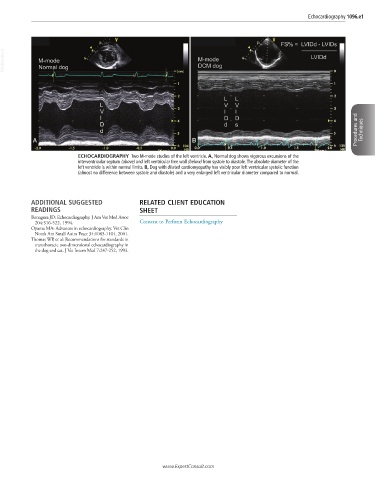

ECHOCARDIOGRAPHY Two M-mode studies of the left ventricle. A, Normal dog shows vigorous excursions of the

interventricular septum (above) and left ventricular free wall (below) from systole to diastole. The absolute diameter of the

left ventricle is within normal limits. B, Dog with dilated cardiomyopathy has visibly poor left ventricular systolic function

(almost no difference between systole and diastole) and a very enlarged left ventricular diameter compared to normal.